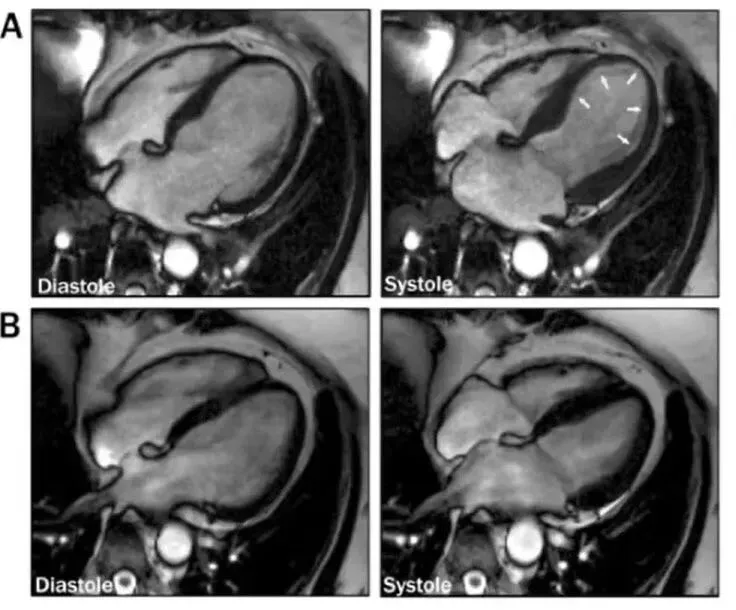

• 心脏超声诊断金标准

经典型:心尖球囊样变(收缩期心尖膨出、基底收缩增强);

变异型:基底型、中间型、局灶型(NSC更多见非心尖型);

弥漫性室壁运动减弱:NSM常见。

推荐床旁超声心动图快速评估心功能,必要时行心脏MRI明确心肌水肿/坏死

根据2024年共识,确诊依赖于影像学(超声/心脏磁共振)显示的特征性室壁运动异常 + 冠状动脉造影的阴性结果

心脏磁共振 日益重要,可用于进一步排除心肌炎、评估心肌水肿和纤维化(TTS通常无延迟钆增强)。